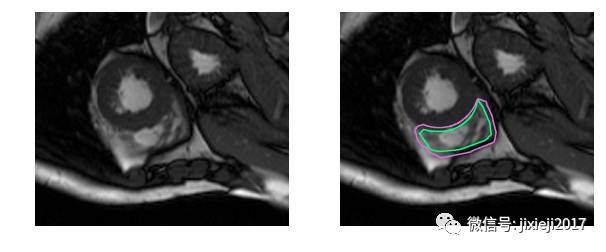

上图的分割较简单。下面是一个比较困难的分割:

不使用医学术语,识别右心室困难的原因是:左心室是一个厚壁的圆柱型区域,而右心室是一个不规则形状的物体,较薄的心室壁有时会与周围的组织混在一起。下图是MRI快照中手工绘制的右心室内壁和外壁(心内膜和心外膜)轮廓: